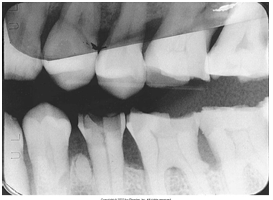

What is the problem with this Overexposed Receptor X-ray?

May occur with digital sensors or film, Excessive exposure time, kilovoltage, or milliamperage, Image appears dark or High density

How would you resolve this Overexposed Receptor X-ray?

Check settings and reduce as needed prior to exposing receptor